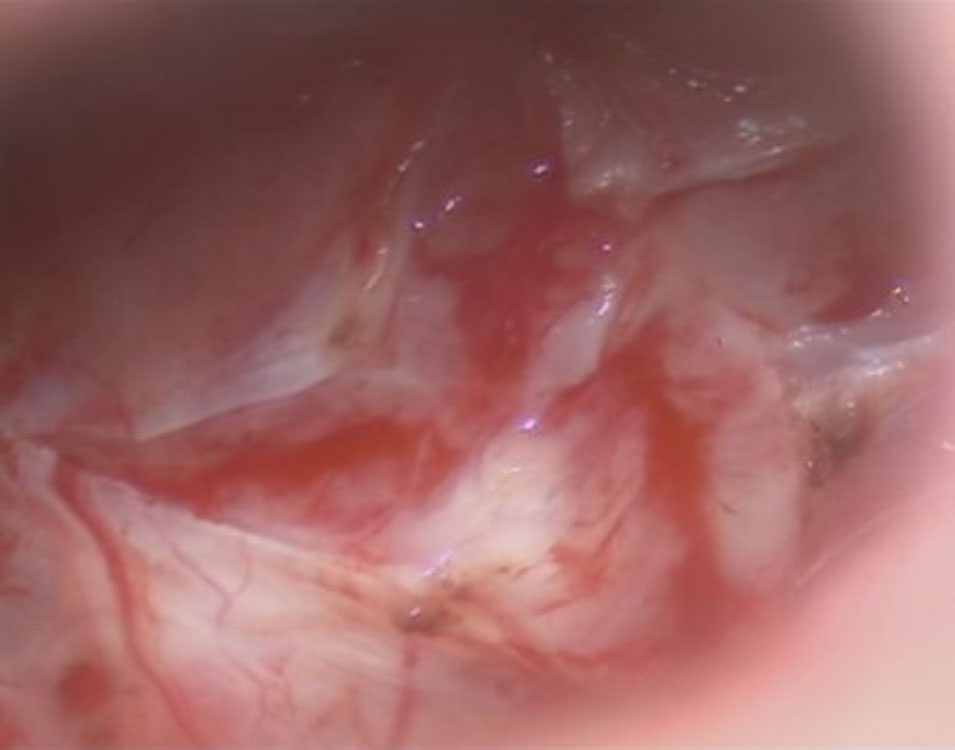

術中写真

摘出 前

摘出 中